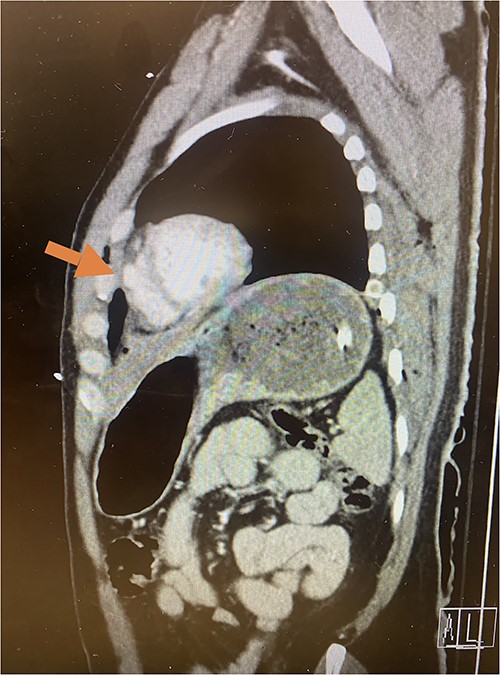

Given his hemodynamic normalization without ongoing transfusion requirements, he was taken to the computed tomography (CT) scanner for axial imaging of the head, chest, abdomen and pelvis. A CT angiogram of the chest revealed trace pneumopericardium and pneumomediastinum with trace hemopericardium. A 1.7 × 0.7 cm out-pouching at the anterior aspect of the right ventricular apex concerning for a traumatic pseudoaneurysm was also detected (see Figs 2 and 3). His other injuries were notable for subarachnoid and subdural hemorrhages, left temporal bone fracture, open mandibular fracture, left 3–6th, 10th and 11th rib fractures, a 4th lumbar vertebrae burst fracture with 1st and 3rd lumbar vertebrae compression fractures, 8–11th thoracic vertebrae compression fractures, and a left femoral neck fracture. He was subsequently transferred back to the trauma bay where a formal trans-thoracic echocardiogram was immediately performed, which demonstrated a dyskinetic area of the right ventricular apex with paradoxical out-pouching during systole—suggestive of pseudoaneurysm and confirming the diagnosis on axial imaging.

Sagittal CT imaging demonstrating pseudoaneurysm of right ventricular free wall rupture.